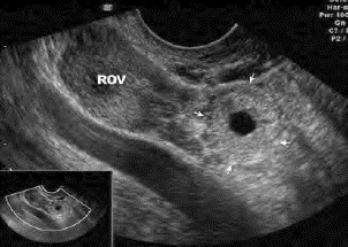

图34-11 宫外孕声像图

右侧卵巢(ROV)旁为输卵管妊娠包块

(2)患侧附件区未破裂之前可见边界清楚、形态规则的肿块,内为低回声,偶可见其中有妊娠囊及胚芽强回声以及原始心管搏动,每分钟140次。彩色多普勒显示肿块周边部有丰富血流(图34-11)。